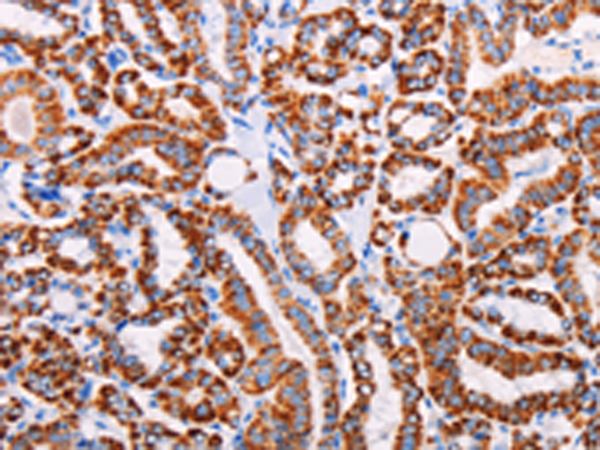

分类: 科研抗体货号: P04245别名: ALDR; ABC39; ALDL1; ALDRP; hALDR应用: IHC反应种属: Human, Mouse, Rat